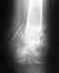

Здравствуйте Нужен совет врача травматолога. Мне 32 года. Четыре с половиной месяца назад поломал плечо, закрытый косой перелом нижней третей плеча. В больнице наложили аппарат Илизарова. Прилагаю снимки недельной давности, меня смущают остаточные смещения, мой врач неуверенно говорит что все будет хорошо. Другой врач предложил провести остеопластику с установкой на костной пластины Хотелось бы услышать ваше мнение что мне в данной ситуации предпринять продолжать лечение аппаратам Илизарова или снятие аппарата с последующей операцией. Надеюсь на ваш ответ.